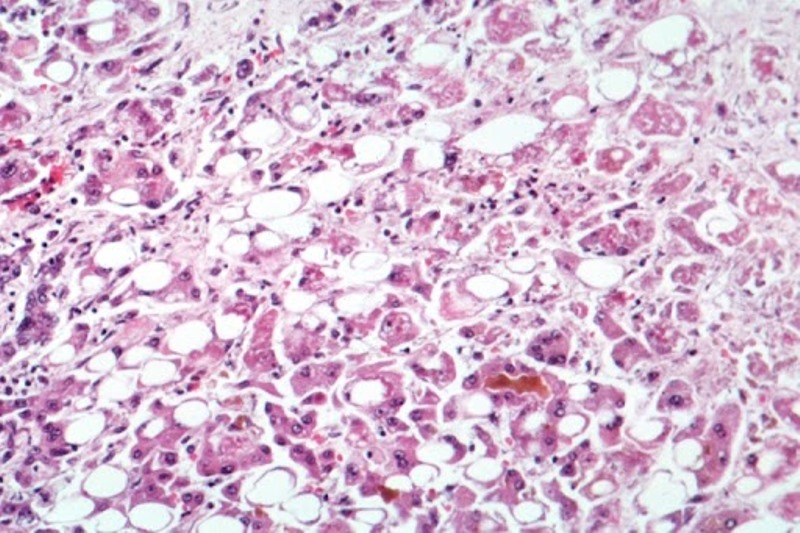

Toronto/IBNS: Cases of severe liver disease "of unknown origin" among children in Canada are being investigated by public health officials as a mysterious hepatitis outbreak has reportedly affected nearly 200 youths around the world.

According to the latest available data from the World Health Organization (WHO), at least 169 cases of acute hepatitis of unknown origin have been reported in close to a dozen countries, with 114 from the United Kingdom.

An even higher estimate of nearly 200 cases in children around the world was reported on Tuesday by the European Centre for Disease Prevention and Control (ECDC).